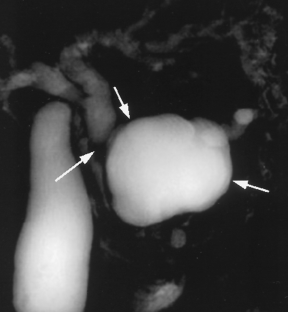

Usual and unusual causes of extrahepatic cholestasis: assessment with magnetic resonance cholangiography and fast MRI

Cholestasis may result from hepatocellular (intrahepatic) disease or biliary tract (extrahepatic) abnormalities. Etiologies causing extrahepatic cholestasis are extremely diverse and invasive procedures, such as endoscopic retrograde cholangiopancreatography (ERCP) and percutaneous transhepatic cholangiography (PTC), were previously required to establish the diagnosis. Due to refinements of magnetic resonance imaging (MRI) techniques, the patient with extrahepatic cholestasis currently can be evaluated noninvasively, and the information revealed frequently exceeds the findings obtained by ERCP and PTC. In this essay, we illustrate the classic MR cholangiographic (MRC) and MRI features of a variety of disorders causing extrahepatic cholestasis, including non-neoplastic disorders of the biliary tract (congenital abnormalities, infectious processes, iatrogenic disorders, and postsurgical complications) and neoplastic conditions (e.g., tumors of the pancreas, biliary tree, liver, ampulla, and regional lymph nodes). In most cases, familiarity with the key MRC features in addition to information obtained via cross-sectional MR images provide sufficient information for adequate lesion characterization.